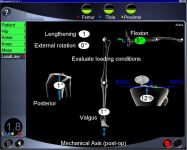

Osteotomie

Korekce osy dolní končetiny navigačním přístrojem Ortho-Pilot

- HTO - korekce osy horního konce holenní kosti

- DFO - korekce osy dolního konce stehenní kosti

- DTO - korekce osy dolního konce holenní kosti